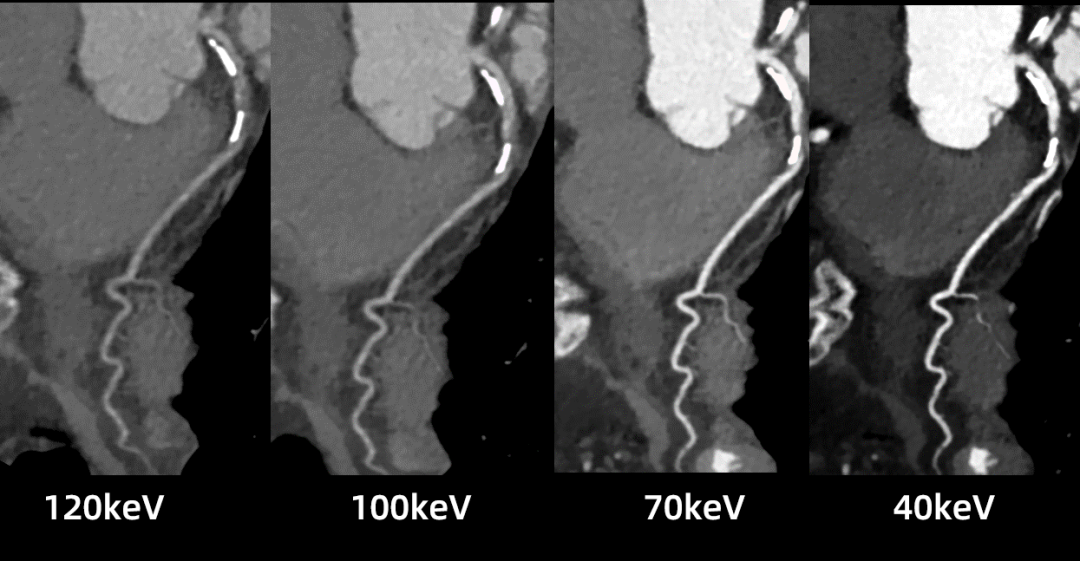

uCT SiriuX落地临床验证中,我们切身体会了这款设备的全脏器覆盖能谱成像功能,可在单心动周期内完成全心能谱采集,提供多种能谱图像类型。

例如,虚拟单能图像可优化冠脉图像对比度,有效消除血管管腔中钙化导致的晕状伪影,确保准确的血管评估;同时,基于能谱图像的物质识别技术,还可进行斑块成分分析,进一步提升诊断精度。

什么是联影ct真香预警?联影医疗双宽体双源CT大揭秘!TA竟然可以看到心脏的高清运动!_https://www.jmylbn.com_新闻资讯_第22张

什么是联影ct真香预警?联影医疗双宽体双源CT大揭秘!TA竟然可以看到心脏的高清运动!_https://www.jmylbn.com_新闻资讯_第23张